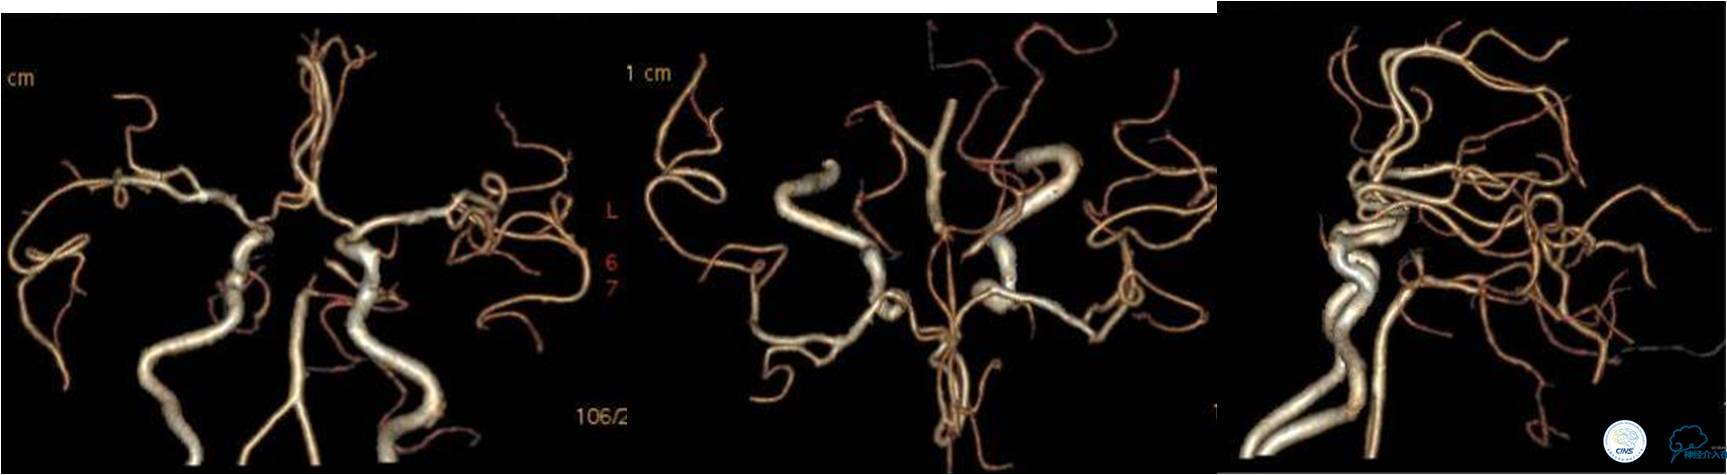

入院时颅脑CTA(发病4小时)